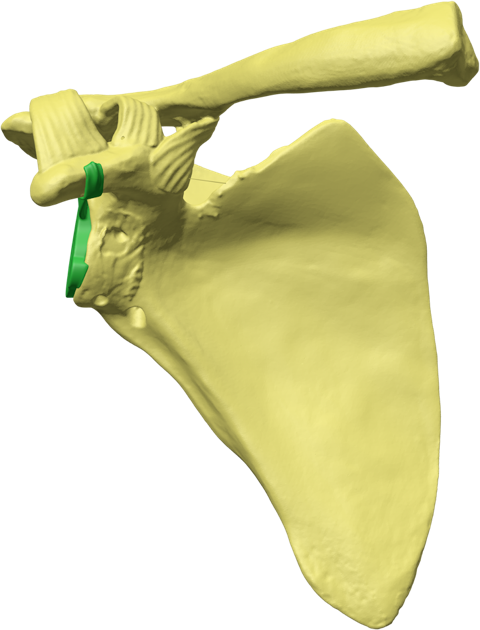

Glenoid Fixation Challenge - Patent No. - US11918476B1

Our innovative design restores anatomic mechanics through enhanced glenoid implant fixation. Using patented Patient Match technology, CT data generate implants matched to variable scapular anatomy, providing immediate fixation that counteracts early rehabilitation forces and supports bone ingrowth into a porous surface for permanent fixation. Improved fixation enables mechanical constraint, supports anatomic shoulder replacement designs, improves motion, and reduces dislocation risk.